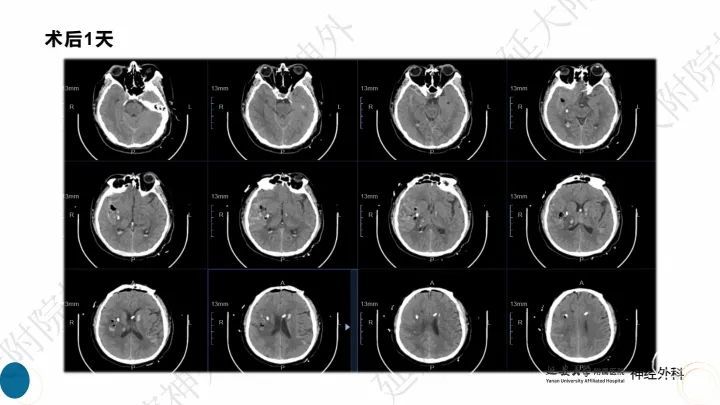

今天为大家分享的是《监测有道丨颅脑创伤-神经重症周刊》第323期,由延安大学附属医院神经外科贾云峰主任医师带来的:右侧基底节区大量脑出血内镜下血肿清除术,欢迎阅读、分享。